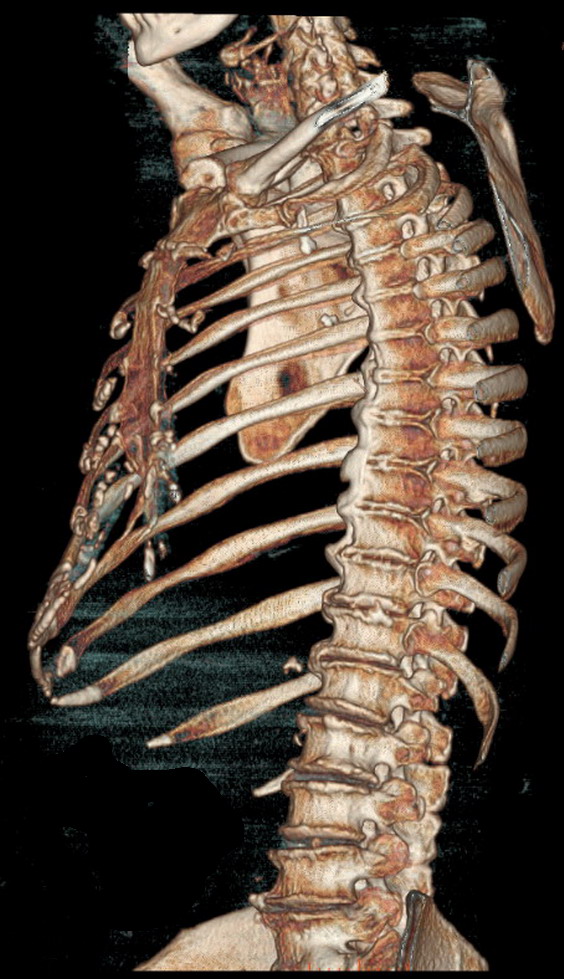

Süňk we bogun inçekeseli.

Öýkenden daşky inçekesel

30

3